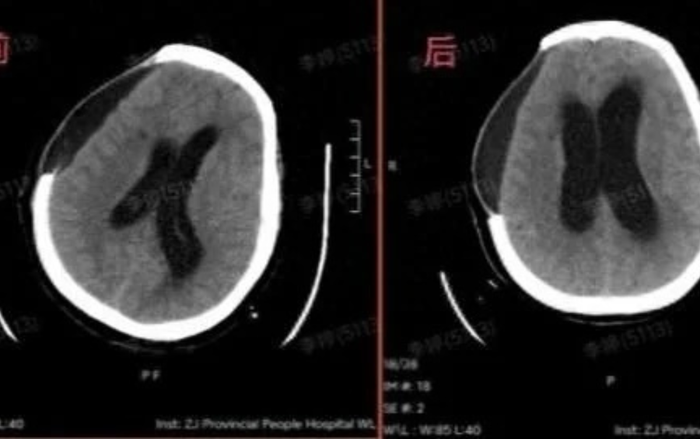

Bà Wang đã được phẫu thuật mở hộp sọ khẩn cấp để loại bỏ máu tụ trong não. Dù ca mổ cứu được tính mạng bệnh nhân, bà vẫn rơi vào hôn mê sâu sau phẫu thuật. Trong quá trình hồi phục, bà còn bị sưng não, tràn dịch nội sọ và viêm phổi nặng.

Qua thời gian dài điều trị bằng các biện pháp như kích thích giác quan, vật lý trị liệu và phẫu thuật bổ sung, bà Wang dần lấy lại được khả năng vận động và nói chuyện một phần. Tuy nhiên, bà vẫn phải đối mặt với tình trạng suy giảm nhận thức nghiêm trọng, mất trí nhớ và phụ thuộc hoàn toàn vào người chăm sóc trong sinh hoạt hằng ngày.